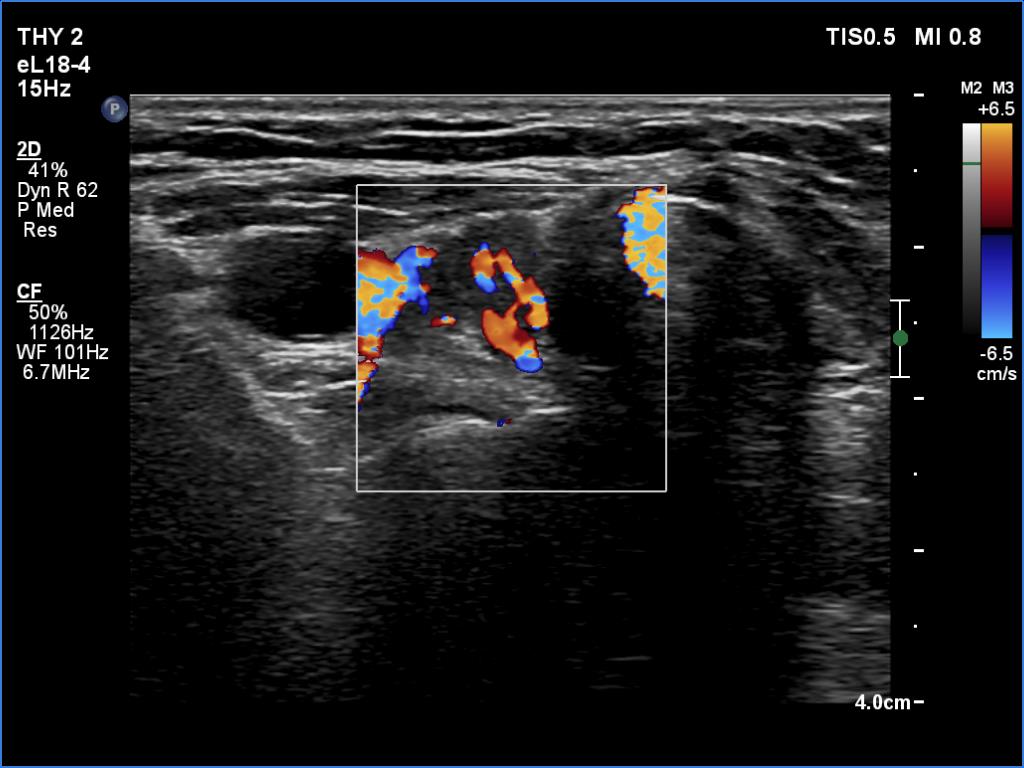

The operated thyroid - case 1563 (ultrasonographic picture 3)

Right lobe, transverse view, color Doppler mode. The lobe has large vessels.